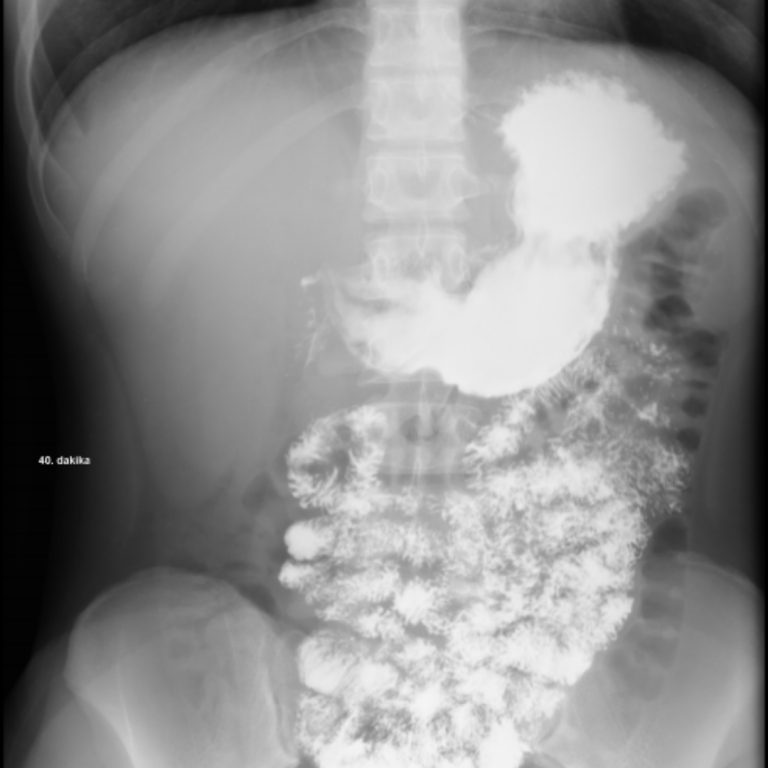

İNCE BARSAK GRAFİSİ

İnce barsakların kontrast madde içirilmesi (ince barsak pasaj grafisi) veya hastaya yutturulan bir tüp aracılığıyla hava ve kontrast madde verilmesi yoluyla (enteroklizis) incelenmesidir. Öncesinde hazirlik gereklidir. Tetkikten önceki 2 gün boyunca, hasta sulu gıdalar almamalıdır. Tetkik öncesinde, en az 12 saatlik açlık ve barsak tamizliği için müshil kullanimı gereklidir.

İnceleme nasil yapılır ?

Hastaya baryumlu kontrast madde içirilerek maddenin ince barsaklarda ilerleyisi doktor tarafindan ekranda izlenir. Kontrast madde kalin barsaklara kadar ilerler ve bu esnada çesitli pozisyonlarda filmler çekilir (Ince barsak pasaj grafisi). Ayrica daha detayli inceleme gerektiren durumlarda hastaya burnundan ince bir tüp yutturulur. Bu tüp, oniki parmak barsagina yerlestirilir ve tüpten kontrast madde ile birlikte hava verilir. Bu sekilde filmler alınır. Çekimin süresi, verilen kontrast maddenin kalin barsağa geçis süresine göre değisir.

Kontrast maddenin çekuma geçiş zamanı tabiidir. İnce barsak segmentlerinin lokalizasyonu mukozal yapısı tabiidir. Duodenum, jejenum genişliği, konturları ve pili yapısı tabiidir. Dolum defekti veya fazlalığı saptanmamıştır. Flokülasyon, segmentasyon ve fragmantasyon izlenmemiştir Terminal ileum kalibrasyonu normal sınırlar içinde olmakla birlikte mukozasında ödematöz paterne ait görünüm dikkati çekmektedir.